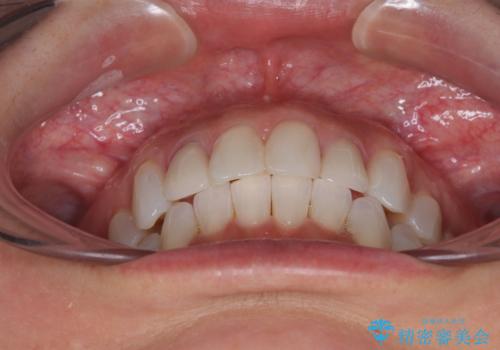

前歯のデコボコとむし歯治療の跡 インビザライン矯正とオールセラミッククラウン治療

- 前歯のセラミッククラウンの縁が見えることが気になってから、デコボコも気になるようになってきたとのことで来院された患者様です。

デコボコの程度は中等度であったため、インビザライン・モデレートパッケージにて歯列を整えることとしました。

セラミッククラウンの装着されていた前歯と、大きな修復治療の跡がある反対側の歯は、矯正治療後に補綴治療を行うこととしました。

奥歯の欠損はインプラント、ブリッジ、入れ歯のどれにすれば良いかを決められず、仕事が非常にお忙しいこともあり、保留としたまま治療を終えることとなりました。

後戻りのリスクがあるため、なるべく早めに欠損補綴治療を開始する予定です。